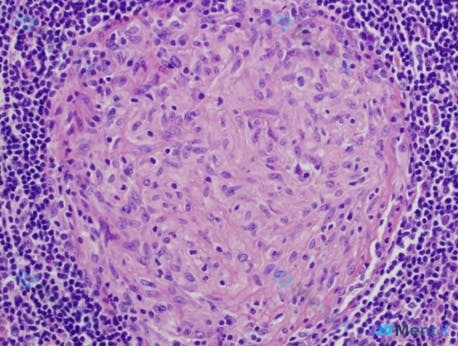

病理结果:经皮活检组织学提示——边界清晰的非坏死性类上皮肉芽肿,周围环绕淋巴细胞袖套,未见干酪样坏死、多核巨细胞及明显恶性特征。

- 光看形态,参与构成这个肉芽肿核心的主要细胞,最可能表达哪种细胞表面蛋白?

📋答案:核心细胞表型:CD14;首选鉴别方向:结节病(需排除感染等)